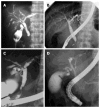

This is a review of the characteristic findings of inflammatory bowel disease (IBD) associated with primary sclerosing cholangitis (PSC) and their usefulness in the diagnosis of sclerosing cholangitis. PSC is a chronic inflammatory disease characterized by idiopathic fibrous obstruction and is frequently associated with IBD. IBD-associated with PSC (PSC-IBD) shows an increased incidence of pancolitis, mild symptoms, and colorectal malignancy. Although an increased incidence of pancolitis is a characteristic finding, some cases are endoscopically diagnosed as right-sided ulcerative colitis. Pathological studies have revealed that inflammation occurs more frequently in the right colon than the left colon. The frequency of rectal sparing and backwash ileitis should be investigated in a future study based on the same definition. The cholangiographic findings of immunoglobulin G4-related sclerosing cholangitis (IgG4-SC) are similar to those of PSC. The rare association between IBD and IgG4-SC and the unique characteristics of PSC-IBD are useful findings for distinguishing PSC from IgG4-SC.